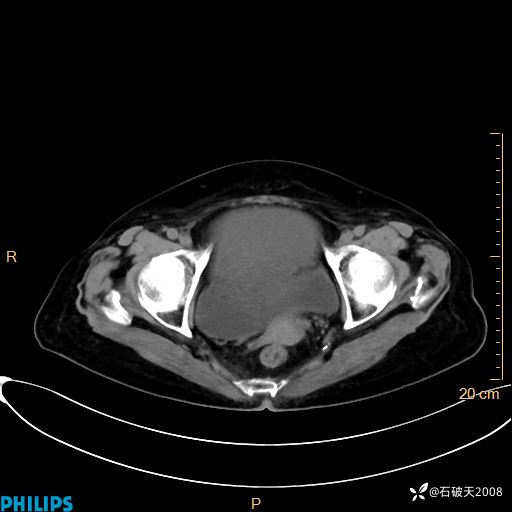

MIP